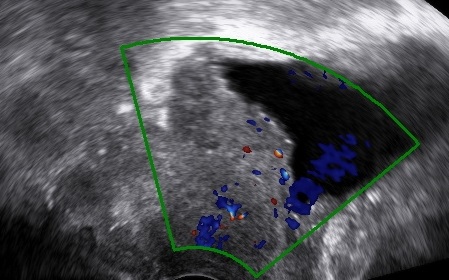

Transvaginal as well as transrectal ultrasound can and should be used in the preoperative work-up of cervical cancer.

It can evaluate the exact location of the tumor, its growth pattern, its size, the extent of invasion and provides the advantage of the dynamic pelvic examination.

Investigate Invasion

a. Partial stromal invasion (tumor – pericervical fascia distance)

b. Complete stromal invasion

c. Parametrial invasion (tumor invades the pericervical fascia laterally)

d. Infiltration of the vesicovaginal septum (tumor invades the pericervical tissue anteriorly)

e. Infiltration of the rectovaginal septum (tumor invades the pericervical tissue posteriorly)

f. Tumor extends to the vagina (fornices are obliterated)